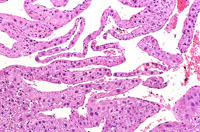

Dilated vascular spaces have replaced hepatic parenchyma in this hemangioma. High magnification shows dilated vascular spaces lined by flattened and sometimes dome-shaped endothelial cells and mild atrophy of the visible hepatic cords.